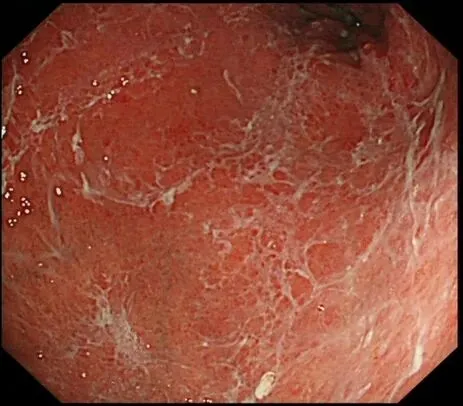

蛛网状黏液case3,服用P-CAB药物(具体服用时长不详)👇